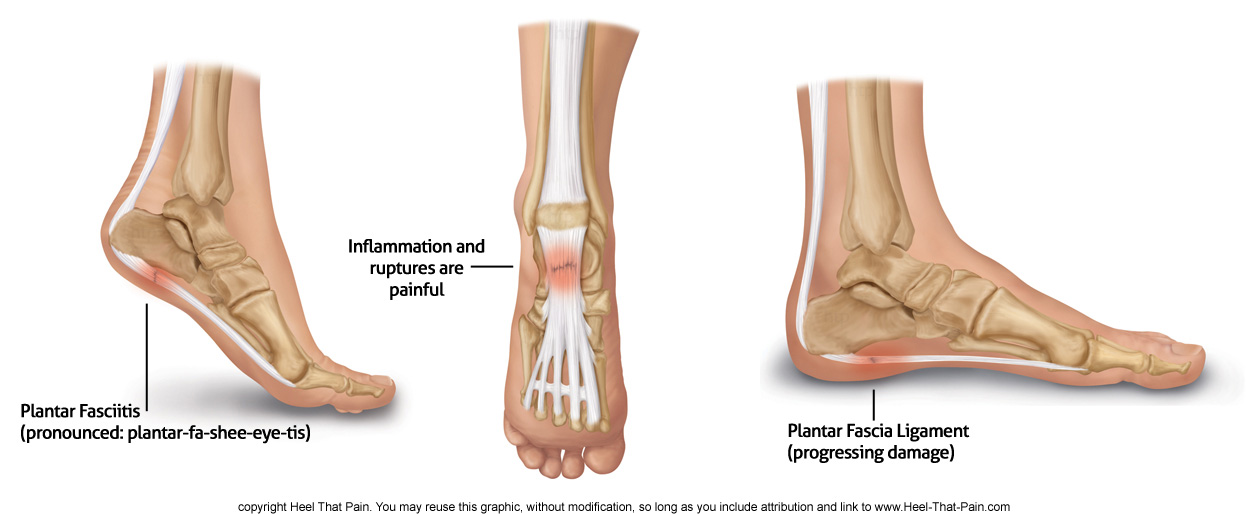

Heel Raise Exercise Progressions My Rehab Connection discount, Piezogenic papules Wikipedia discount, Achilles Tendinitis OrthoInfo AAOS discount, Bilateral calcaneal apophysitis Radiology Case Radiopaedia discount, duet with followtheeve No those are not tumors and vast majority are asymptomatic. toppodiatry podiatry whatisthat normal discount, Plantar fasciitis Symptoms and causes Mayo Clinic discount, OrthoDx Bilateral Painful Feet Clinical Advisor discount, Stretches for Heel Pain by Sydney Heel Pain Clinic discount, Bilateral Piezogenic Papules of the Heel A Comprehensive Understanding CE Foot Ankle Clinic Nashville discount, A 31 y.o. male comes in with bilateral heel pain. His xray is shown below WashU EM Blog discount, Plantar Heel Pain Physiopedia discount, Diagnosing Heel Pain in Adults AAFP discount, Calcaneus Fracture Broken Heel Bone Orthopaedic Trauma Association OTA discount, Managing the patient with heel pain British Journal of Hospital Medicine discount, How to Secure a VA Rating for Bilateral Heel Spurs discount, What is Plantar Fasciitis Causes Symptoms Treatment discount, Bilateral heel with right sided calcaneal spur. Normal plantar fascia. Download Scientific Diagram discount, Posterior heel pain Chelsea and Westminster Hospital NHS Foundation Trust discount, A Bilateral masses on the patient s Achilles tendons. B C Ankle MRI. Download Scientific Diagram discount, Heel Pain causes and treatment plantar fasciitis diagnosis and treatment discount, Pain In The Back Of The Heel What Could It Mean discount, Standing Bilateral Heel Raises discount, Bilateral broken calcaneal spurs BMJ Case Reports discount, Standing Bilateral Heel Raises discount, Exercise Bilateral Heel Raise with Eversion discount, Diagnosing Heel Pain in Adults AAFP discount, Plantar fasciitis treatment symptoms and causes healthdirect discount, Bilateral heel raises 1 year after right Achilles tendon removal. Download Scientific Diagram discount, Heel Pain Diagnosis and Management AAFP discount, Diagnosing Heel Pain in Adults AAFP discount, Radiological investigation shows bilateral heel spurs A X ray of the. Download Scientific Diagram discount, X Ray Bilateral Heel AP View and Lateral Test Price in Delhi Ganesh Diagnostic discount, Bilateral Heel Drop by Joshua Feinberg Exercise How to Skimble discount, Heel Pain Causes Treatments and Home Remedies Heel That Pain discount, Appearance 1.5 years after surgery. A Bilateral heels are preserved. B. Download Scientific Diagram discount, Product Info: Bilateral heels discount.